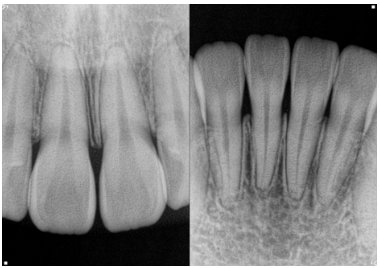

먼저 구내 촬영과 파노라마 촬영을 통해

매복된 치아의 정확한 위치와 방향을 파악합니다.

또한 3D CT 촬영으로 뼈의 상태와

주변 조직과의 관계도 정확히 분석하죠.

22.03.26

절단연 교합의 경우,

단순히 치아 배열만의 문제인지

아니면 골격적인 문제를 동반하는지

감별해야 됩니다.

골격적인 문제를 동반하면

치료 방법이 달라질 수 있거든요.

심각한 치근 흡수 문제는

흡수 정도를 정확히 측정하여

해당 치아를 살릴 수 있는지 여부를

결정해야 됩니다.